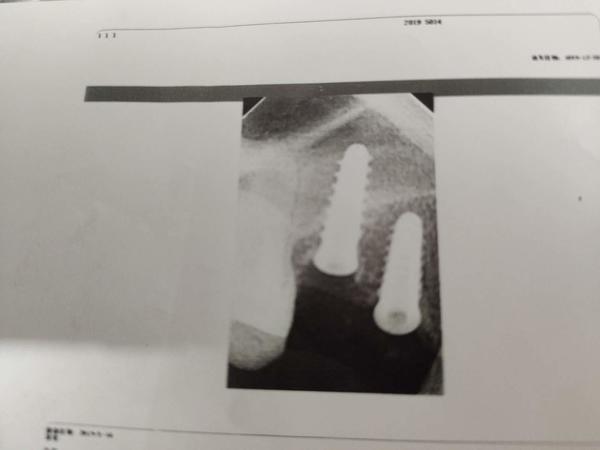

2019年下半年,在出现了不适反应后,叶女士到沈阳一家部队医院口腔门诊求医。经CT等检查,她才发现,原来有一颗种植体已经进入了她的上颌窦腔。

叶女士做出的影像检查结果显示,其中一颗植体已经进入上颌窦腔内。

“有大医院医生告诉我,这就是说,种植体把我上颌窦腔打穿,口腔和鼻腔连通了!”叶一帆说,她随后了解得知,袁克伟并不具备种植牙的技术水准,而且执业地点也不在天丽口腔,且天丽口腔诊所也不具备种植牙这一诊疗项目,“我是被他当成小白鼠了”。

2019年7月,在出具的诊断证明上,沈阳市当地一家三甲医院的知名口腔诊疗专家说,该种植体已经进入上颌窦腔,需要取出。